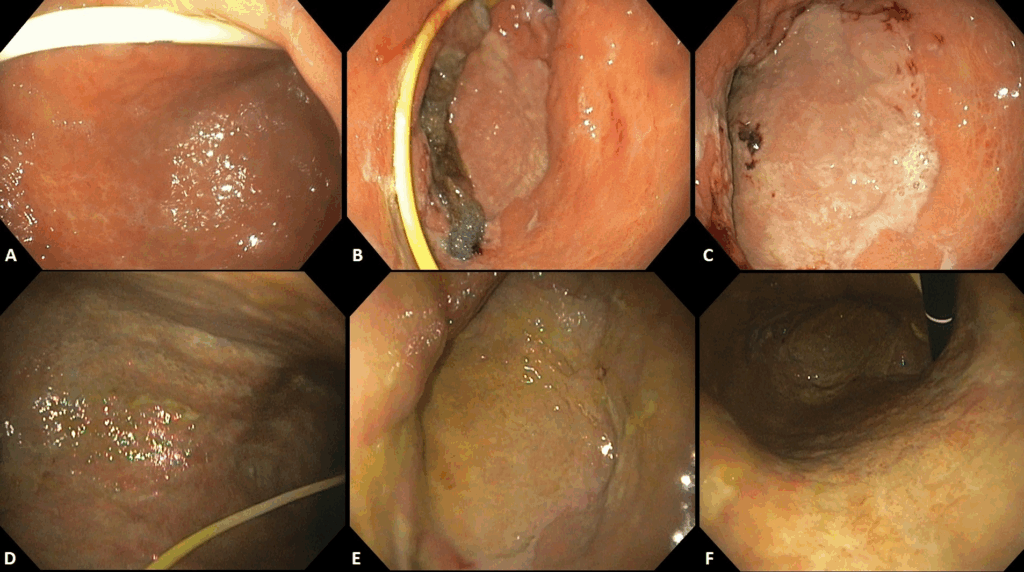

Figura 1 Adaptado de Moura et al (7): Sangrado duodenal difuso en pacientes con COVID-19 antes y después del tratamiento endoscópico al vacío

En 2022, Moura et al. [7] publicaron una serie de tres casos con excelentes resultados para el control de hemorragia duodenal difusa en pacientes críticos con COVID-19. Más recientemente, el mismo gran grupo amplio esa experiencia publicó una serie de 19 casos de HDA no varicosa tratados con TVP [8].